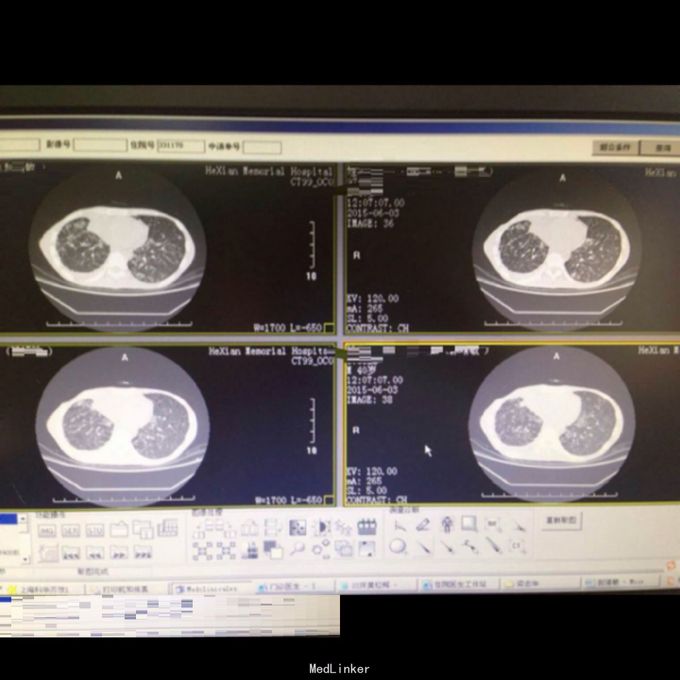

体查:T:36.9℃ R: 23次/分 P:86次/分 BP:130/70mmHg,消瘦,自主体位,神志清楚,对答切题,查体合作。皮肤粘膜未见苍白、黄染,未见皮疹,无皮下出血点,无伤口。全身浅表淋巴结未扪及肿大。口唇红润,伸舌居中,咽部无充血,扁桃体无肿大。颈软,无抵抗,颈静脉无充盈,肝颈静脉回流征(-),气管居中,胸廓对称无畸形、无局部膨隆或凹陷。呼吸平稳,节律规则。双侧呼吸动度对称。双肺部叩诊清音。双肺呼吸音清,双肺未闻及干湿性啰音。心界不大,心率86次/分,律齐,各瓣膜区未闻及病理性杂音。 辅助检查: 双肺CT:1、双肺弥漫性病变,考虑继发型结核,并双肺上叶、下叶背段多发空洞形成、支气管扩张,建议治疗后复查。2、双侧胸膜增厚、粘连,右侧少量胸腔积液。

诊断: 支气管哮喘急性发作、慢性阻塞性肺气肿 治疗:入院后予吸氧抗炎化痰止咳对症支持治疗,并行支纤镜吸痰:找到抗酸杆菌,患者病情好转,予转慢病站继续治疗。